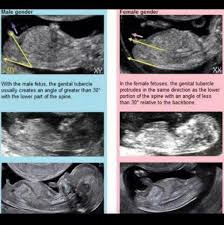

Typically anywhere past 16 weeks is when you can tell. Getty contributor the nub theory. If it is a boy it is boy. If it is moving upward then it is more likely a boy.

The flow of urine can sometimes be spotted in a fetus. Well my sonographers were definitely focussed on the medical side of this scan and rightly so. Genetic testing through cvs remains the most accurate way to determine fetal sex in the first trimester. The gender of your baby is revealed at your second scan between 18 and 21 weeks but there s another test people use to determine if it s a boy or girl credit.